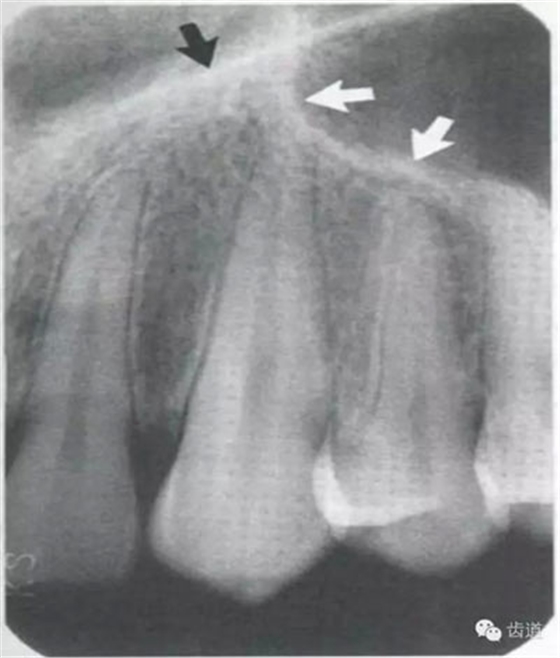

牙頸部Burnout征象:有時(shí)因投照技術(shù)問(wèn)題而造成牙頸部近中或遠(yuǎn)中呈低密度影像,位于牙釉質(zhì)和牙槽嵴頂之間。

在兩個(gè)中切牙牙根之間或稍上方,多呈橢圓形密度低的影像,切牙孔影像可重疊在一側(cè)中切牙牙根尖處,易誤認(rèn)為根尖周病變,可視牙周膜和骨硬板是否完整加以鑒別

位于兩側(cè)中切牙牙根之間,由牙槽突向上,呈直線狀密度低的影像。其兩側(cè)為密度高的影像,為兩側(cè)上頜骨腭突的致密骨層。

鼻腔位于上切牙根尖的上方,顯示為對(duì)稱性半圓形密度低的影像,其中間被一密度高的骨隔分開(kāi)為鼻中隔